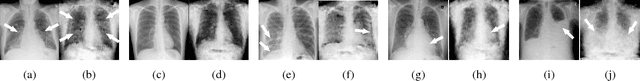

Medical datasets are often highly imbalanced with over-representation of common medical problems and a paucity of data from rare conditions. We propose simulation of pathology in images to overcome the above limitations. Using chest X-rays as a model medical image, we implement a generative adversarial network (GAN) to create artificial images based upon a modest sized labeled dataset. We employ a combination of real and artificial images to train a deep convolutional neural network (DCNN) to detect pathology across five classes of chest X-rays. Furthermore, we demonstrate that augmenting the original imbalanced dataset with GAN generated images improves performance of chest pathology classification using the proposed DCNN in comparison to the same DCNN trained with the original dataset alone. This improved performance is largely attributed to balancing of the dataset using GAN generated images, where image classes that are lacking in example images are preferentially augmented.